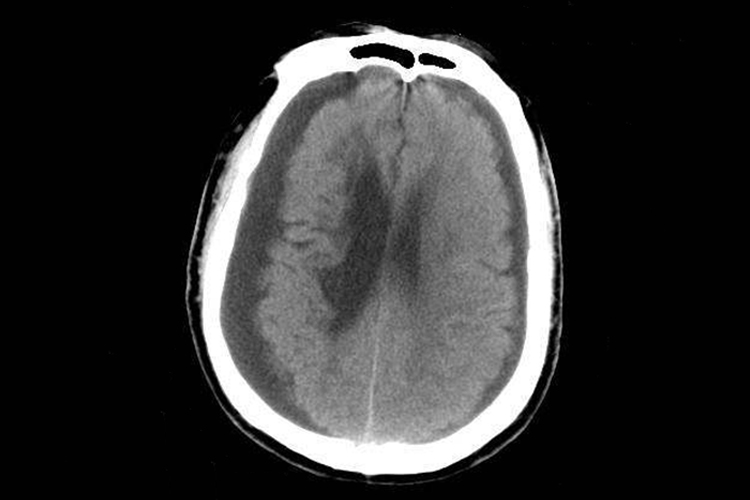

硬膜下血肿ct可见局部有高密度影,少数为等密度、低密度影。

硬膜下血肿的CT影像与发病类型有关,急性硬膜下血肿的CT大多表现为颅板下方的新月形高密度影,亚急性或慢性硬膜下血肿的CT可表现为高密度、等密度、低密度或混杂密度影。此外还常伴随昏迷、头痛、呕吐等症状。